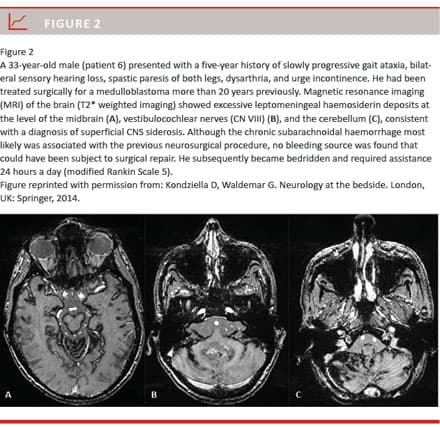

In the “classic” or “infratentorial” type of superficial CNS siderosis, subpial haemosiderin deposits of the brain and spinal cord accumulate due to chronic subarachnoid haemorrhage, often causing progressive ataxia, deafness, dementia and sometimes a bed-ridden helpless state (Figure 1 and Figure 2) [1-9]. Many different conditions can lead to this form of superficial CNS siderosis, including congenital malformations such as fluid-filled collections in the spinal canal, CNS tumours, post-neurosurgery, head or back trauma, arteriovenous malformations and brachial plexus/root injuries [4, 5]. Surgical removal of the bleeding source remains the only causative treatment option. However, knowledge about treatment outcomes is scarce and typically derived from single case reports [1, 3, 5-9]. We therefore present a consecutive case series from a tertiary neuroscience centre in order to stress the challenges related to diagnosing and treating patients with superficial CNS siderosis.

A potential bleeding aetiology was identified in all patients. Five patients (56%) had an acquired bleeding; three patients had road traffic accidents leading to brachial plexus (n = 1), respectively, cervicothoracic nerve root avulsions (n = 2), one patient had an odontoid fracture during childhood, and another patient had been operated upon for a medulloblastoma. The mean delay from injury to first symptoms was 17.5 ± 12.5 years. Three patients (33%) had congenital bleeding sources, including spinal arachnoid cysts (n = 2) and brain malformations (n = 1). One patient (11%) had both a possible congenital (thoracic arachnoid cyst) and an acquired bleeding source (previous neurosurgery for a medulloblastoma).

As our data show, identifying a potential bleeding aetiology (e.g. a previous traffic accident) does not necessarily mean that an active bleeding can be found, and definitive surgical removal of the culprit bleeding source is achieved only rarely. Nevertheless, patients may deteriorate, probably because neurodegeneration induced by haemosiderin-associated iron toxicity becomes irreversible [2, 3]. Important mechanisms, akin to those seen in other neurodegenerative disorders such as Alzheimer’s disease, include hyperphosphorylation of tau protein and oxidative stress [3]. Despite post-surgical decrease of CSF bleeding derivatives in all three patients in whom a bleeding source was removed, two patients (66%) continued to deteriorate. This suggests a point-of-no-return when critical amounts of haemosiderin have accumulated [2, 3]. It remains unknown why some patients apparently tolerate larger amounts of haemosiderin deposits than others, but genetic factors may play a role [6]. Furthermore, some patients with superficial CNS siderosis clearly suffer from concurrent brain pathologies, which contribute to their neurological decline, e.g. patients 6 and 9 with a history of radiation and chemotherapy for a medulloblastoma. However, the point-of-no-return hypothesis of haemosiderin accumulation is supported by e.g. patient 4 who progressed clinically despite serial MRI showing unchanged amounts of haemosiderin during a period of 11 years.